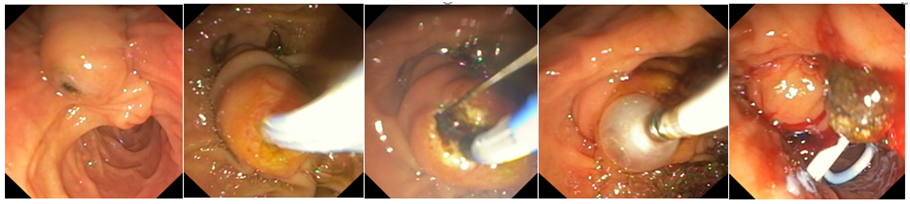

ERCP (Endoscopic Retrograde Cholangiopancreatography) is a specialized procedure used to diagnose and treat conditions affecting the bile ducts, gallbladder, and pancreas. Problems such as bile duct stones, blockages, strictures, and recurrent jaundice often require ERCP for accurate diagnosis and effective relief.

At Sapphire Gastroenterology Center, ERCP is performed with advanced technology to safely remove stones, relieve obstructions, and place stents when needed. This helps reduce pain, prevent infections, and avoid major surgery in many cases. Early ERCP intervention can prevent serious complications such as cholangitis, pancreatitis, and long-term liver damage.